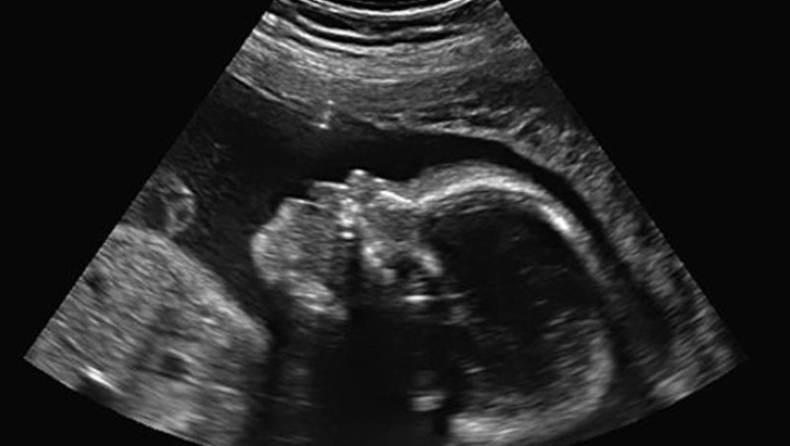

Νόμιζε πως ήταν έγκυος, αλλά είχε θανατηφόρο όγκο στην μήτρα!

Μια 22χρονη Βρετανίδα κατέληξε τον περασμένο μήνα, αφού οι γιατροί πέρασαν έναν καρκινικό όγκο μεγέθους σχεδόν 10 εκατοστών για... έμβρυο!

Αυτό που επακριβώς διέγνωσαν οι γιατροί ήταν «μύλη κύηση», η οποία αρχικά συμπεριφέρεται σαν ομαλή εγκυμοσύνη και εμφανίζεται ως τέτοια βάσει των εξετάσεων της ορμόνης εγκυμοσύνης, ενώ προκαλεί την αύξηση του μεγέθους της μήτρας. Μόνο κατά την 12η εβδομάδα της κύησης μπορεί να διαγνωσθεί ως τέτοια, σύμφωνα με τους ειδικούς που μίλησαν στο usatoday.